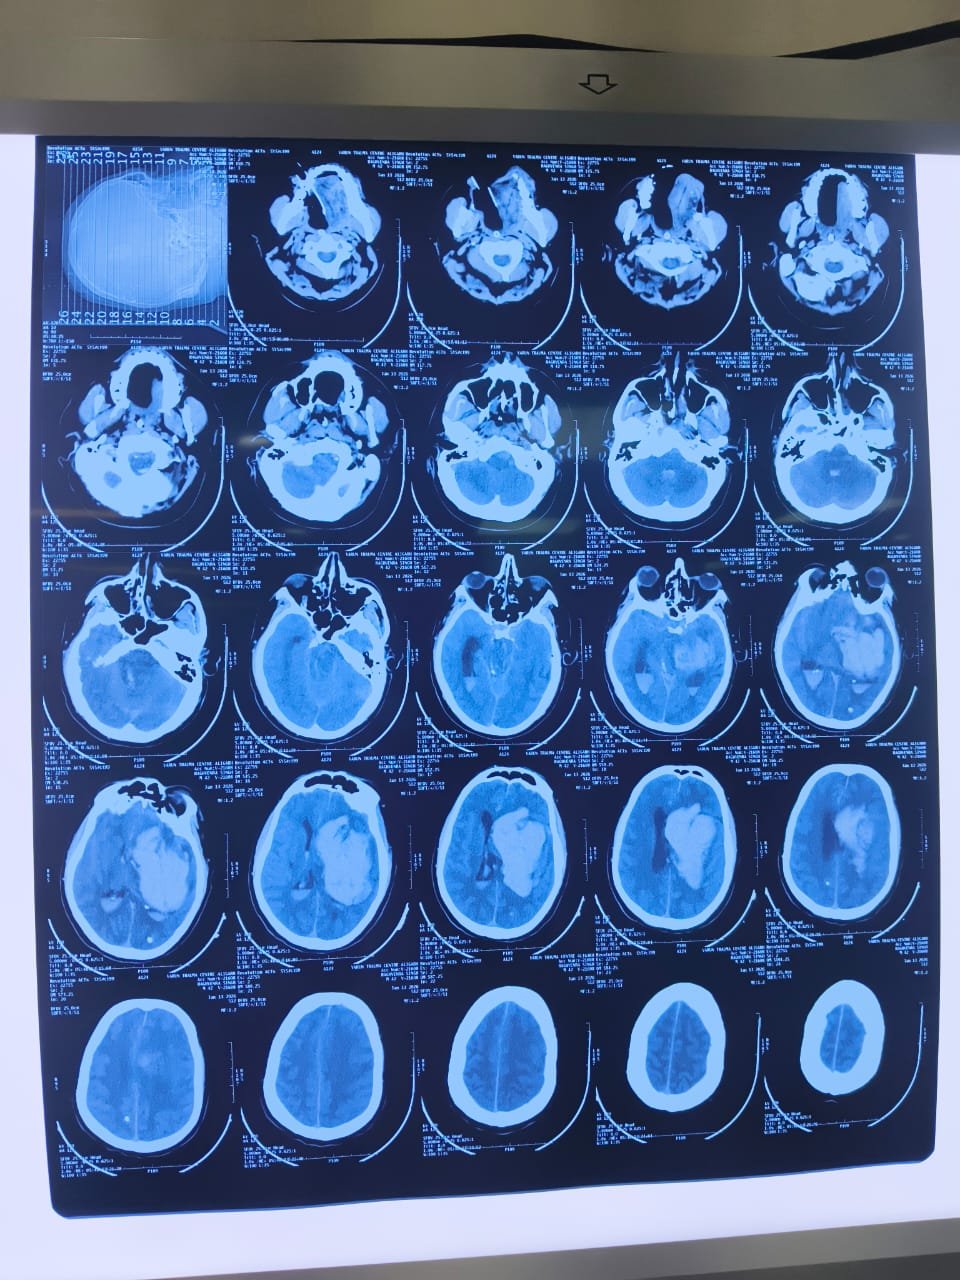

At LeftyNeurosurgeon, we specialize in providing cutting-edge neurosurgical care for brain and spine health. Led by Dr. Deepak Lohia, a recognized leader in Minimal Invasive Neurosurgery and Neuroendovascular Surgery, we are dedicated to transforming lives through advanced treatments and compassionate care.

Our clinic combines state-of-the-art technology with years of expertise to offer precision-based surgeries that ensure faster recovery, reduced risks, and improved outcomes for our patients. We focus on minimizing discomfort and maximizing recovery, utilizing minimally invasive techniques wherever possible.

Minimally invasive neurosurgery involves performing surgeries with small incisions and using advanced technology, resulting in less pain, quicker recovery, and minimal scarring compared to traditional surgery methods. It’s used for brain and spine surgeries, including tumor removal and spinal decompression.